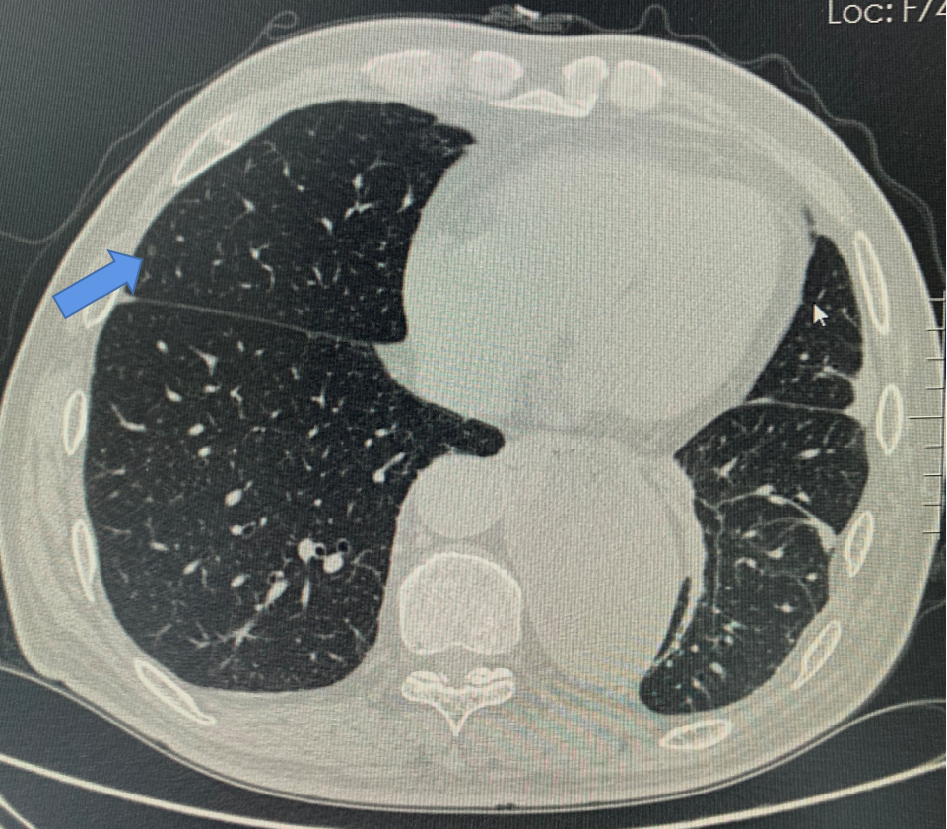

肺微小结节(这里指<5mm结节)

肺小结节近年来越来越受到临床医生重视,因为很多小结节其实是早期肺癌。

但是,随着科技的提高,CT扫描已经能够发现1mm左右的结节,再加上这两年人工智能的应用,使得肺小结节在CT报告上的出现率“泛滥成灾”。再加上很多人宁可错杀一千,不可放过一个的心态,导致紧张情绪蔓延。甚至连我周围的同事都出现过这种情况,问医生A,说不能确定良恶性,医生B说可以观察,医生C说先不用管,自己家人说要不切了吧,省的闹心!!

其实,在最新的国际肺小结节指南上已经把事情说得很清楚了,总结下来就是,对于5mm左右的小结节,随访就可以了(不同长相的小结节具体方法不同,但最严重的3个月后再次复查薄层CT就可以了,这里不包括1cm左右的混合磨玻璃结节或者其他有明显恶性征象的结节)。总得来说,是个事儿,需要上心,但离癌症还有不小的距离。

右肺中叶微小结节。需要半年复查